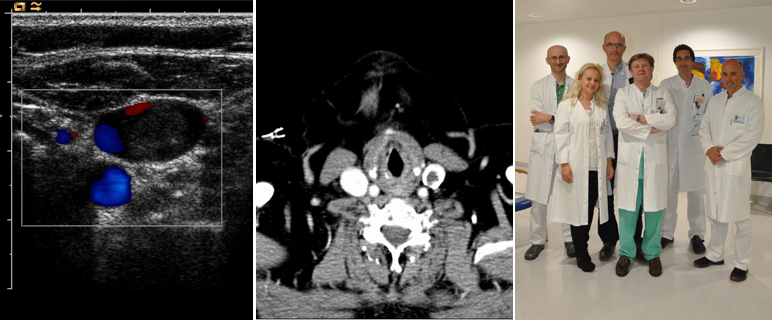

Tiefe Venenthrombosen sind weit verbreitet: Jährlich sind rund zwei bis drei von 1.000 Personen davon betroffen. Eine rasche Abklärung einer Venenthrombose ist notwendig, um schwerwiegende Komplikationen zu verhindern. Zu den Folgen zählt beispielsweise eine Lungenembolie, welche die dritthäufigste kardiovaskuläre Todesursache darstellt. Rund zehn Prozent der Thrombosen betreffen die Armvenen, wesentlich häufiger sind akute tiefe Bein- und Beckenvenenthrombosen. Da die Symptome einer Thrombose häufig diffus sind, gibt es für Thrombosen im Bein- und Beckenbereich ein Risikoscore-System, um die Wahrscheinlichkeit der Diagnose zu erhöhen. Dabei wird das Vorliegen verschiedener Risikofaktoren, wie beispielsweise einer akuten Krebserkrankung, längere Bettruhe oder eine Schwellung der Beine mitberücksichtigt. In Verbindung mit einem D-Dimer Test, einer Blutuntersuchung über die Abbauprodukte von Thromben festgestellt werden, und einer Ultraschalluntersuchung kann eine tiefe Bein- und Beckenvenenthrombose ausgeschlossen werden. Für die wesentlich schwerer zu diagnostizierende tiefe Armvenenthrombose liegt bisher allerdings kein entsprechender Algorithmus vor. Dementsprechend sind hier für die Diagnose oft weitere aufwendige diagnostische Schritte, wie eine CT oder MRT-Untersuchung mit Kontrastmittel oder auch eine Venographie notwendig.

Durch die aktuelle Forschungsarbeit, an der neben der Innsbrucker Univ.-Klinik für Innere Medizin III (Direktor: Univ.-Prof. Dr. Wolfgang-Michael Franz) weitere 15 Kliniken in Europa und den USA beteiligt waren, liegen nun zusätzliche Erkenntnisse zur Entwicklung einer nichtinvasiven Vorgehensweise für die Diagnostik einer Armvenenthrombose vor. Innsbrucker WissenschaftlerInnen um ao.Univ.-Prof. Dr. Peter Marschang beschäftigen sich bereits seit Jahren mit der Diagnose und Behandlung von tiefen Armvenenthrombosen und sind aufgrund ihrer Referenzen an dieser vom Academic Medical Center Amsterdam aus koordinierten Studie beteiligt gewesen. „Durch den weitverbreiteten Einsatz von zentralen Venenkathetern verzeichnen wir in den vergangenen Jahren eine steigende Anzahl von Armvenenthrombosen“, erklärt Marschang den Hintergrund der aktuellen internationalen Forschungskooperation. Insgesamt wurden die Daten von rund 406 PatientInnen ausgewertet. Während bisher zur Abklärung oft aufwendige oder für die Patienten belastende Untersuchungen notwendig waren, zeigen die aktuellen Studienergebnisse, dass die Kombination eines Risiko-Score-Systems mit dem D-Dimer-Test und einer Ultraschalluntersuchung ein hohes Potential hat, eine tiefe Armvenenthrombose sicher auszuschließen, ähnlich dem Vorgehen bei einer tiefen Bein- und Beckenvenenthrombose. Die Erkenntnisse dienen als Voraussetzung für weitergehende klinische Studien mit dem Ziel einen Diagnose-Algorithmus für PatientInnen weltweit zu entwickeln.